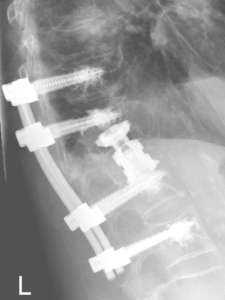

Stabilisierende Operationen

Zeigt sich ein höhergradiger Verschleiß bzw. eine ausgeprägte Instabilität, wird der betroffene Wirbelsäulenabschnitt versteift (Fusion). Kombiniert mit diesem Verfahren kann ggf. auch eine Erweiterung des Wirbelkanals (Dekompression) bei Verengung (Spinalstenose) erfolgen.

Wirbelkörperersatz

Bedingt durch eine Entzündung, einen Bruch oder eine Tumorerkrankung kann ein Wirbelkörper vollständig zerstört werden. Durch einen Platzhalter wird der betroffene Wirbelsäulenabschnitt rekonstruiert und stabilisiert.